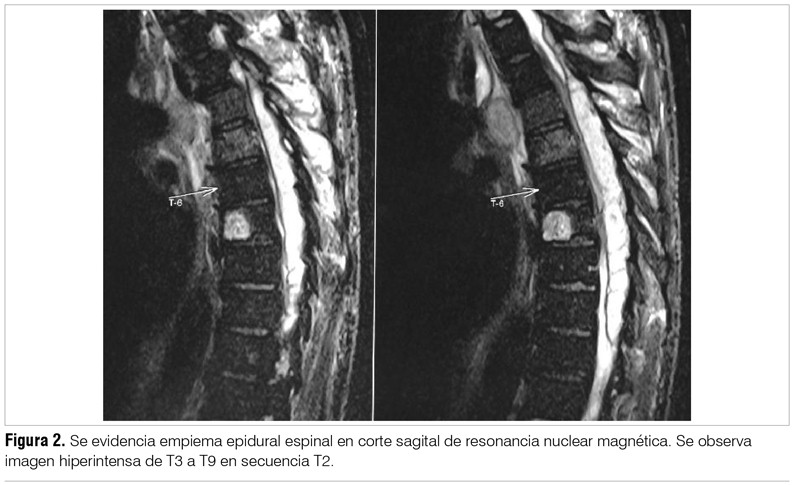

Paciente de sexo masculino, de 54 años, diabético. Presentaba antecedente de drenaje de absceso glúteo en el mes previo, con cultivo a Staphylococcus aureus meticilino sensible, desconociendo cuál fue el tratamiento antibiótico realizado en ese momento. Consultó por dolor raquídeo dorsal de 20 días de evolución, asociando déficit motor de MMII y retención aguda completa de orina. Al ingreso presentaba mal estado general y temperatura axilar de 38 °C. La exploración neurológica mostró paraparesia crural severa a predominio de miembro inferior izquierdo y nivel sensitivo en T4. Se realizó RM de columna toraco-lumbar que objetivó colección epidural posterior T2-T10 con compresión del cordón medular. Múltiples colecciones asociadas a nivel paravertebral y osteítis a nivel T4-T5 (figura 2). Se realizó neurocirugía decompresiva y drenaje de la lesión, confirmándose EEE. Se asoció tratamiento antibiótico empírico en base a vancomicina, ceftazidime y metronidazol intravenosos durante seis semanas. El cultivo del material extraído no mostró desarrollo microbiológico. En la evolución presentó mejoría de la paraparesia que logró vencer la gravedad. Persistió con el trastorno esfinteriano de forma permanente. En la tabla 1 se destacan los hallazgos analíticos.